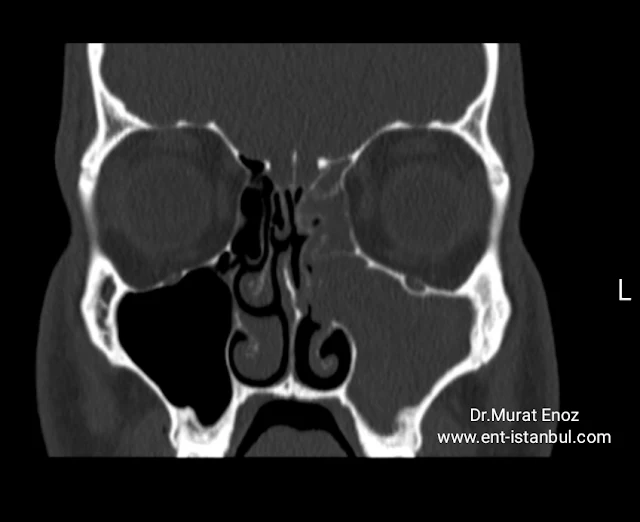

Diagnosis of Sinusitis

![]() |

| Sinusitis Diagnosis |

Acute sinusitis can be diagnosed with patient's symptoms and

endoscopic examination of the nose.